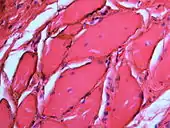

If necessary, the diagnosis can be confirmed histologically by excisional biopsy, which excludes nevi and melanomas.[3]: 138 If a biopsy is taken, the histopathologic appearance is:[1]

- Pigmented fragments of metal within connective tissue

- Staining of reticulin fibers with silver salts

- A scattered arrangement of large, dark, solid fragments or a fine, black or dark brown granules

- Large particles may be surrounded by chronically inflamed fibrous tissue

- Smaller particles surrounded by more significant inflammation, which may be granulomatous or a mixture of lymphocytes and plasma cells